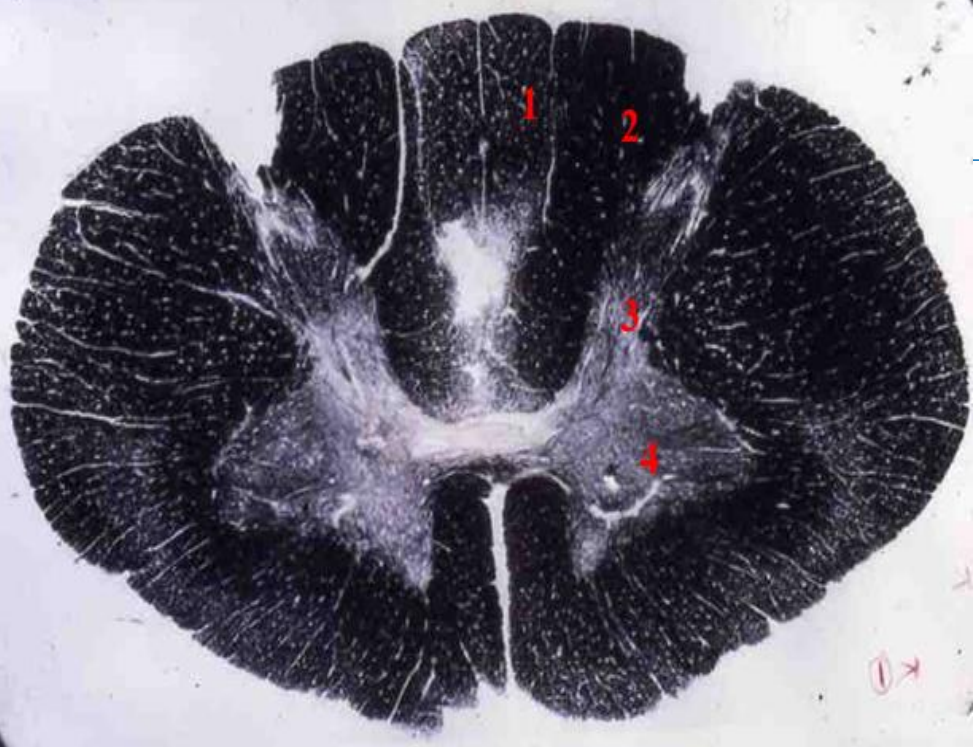

4

5

Perfectly

Q

3

A